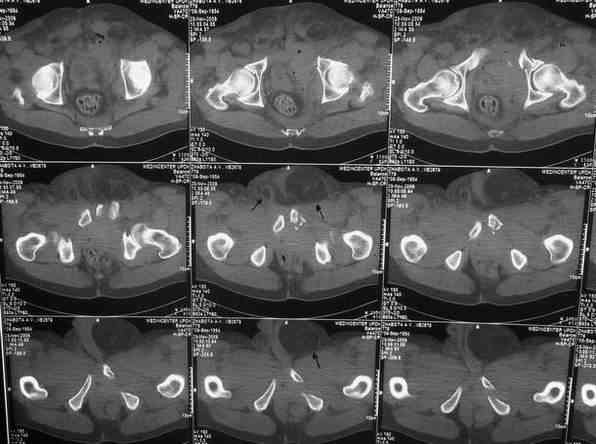

Уважаемые коллеги. У больного оскольчатые переломы левых лонной и седалищной костей со смещением, разрывом симфиза и распространением линии перелома на вертлужную впадину; переломы крыла левой подвздошной кости и правой боковой массы крестца без смещения; разрыв уретры. За последние годы пациент 6 раз оперирован на передней брюшной стенке (гнойный аппендицит срединным доступом, вентральная послеоперационная грыжа и паховые грыжи с обеих сторон, оперированные по 2 раза каждая). Остались 3 грубых втянутых рубца после этих операций. В настоящее время имеются 2-сторонние паховомошоночные грыжи (на одной из КТ-грамм указаны стрелками), из которых левая - значительных размеров. Мошонка огромная, однако, не напряженная. Состояние больного на сегодняшний день относительно удовлетворительное, кровопотеря компенсирована, мочевой пузырь катетеризирован. Прошу мнения сообщества по следующим вопросам: выполнять ли в таких условиях остеосинтез? Если да, то в какой последовательности (отдельно или одним этапом с герниотомией)? Объем остеосинтеза? Доступ?